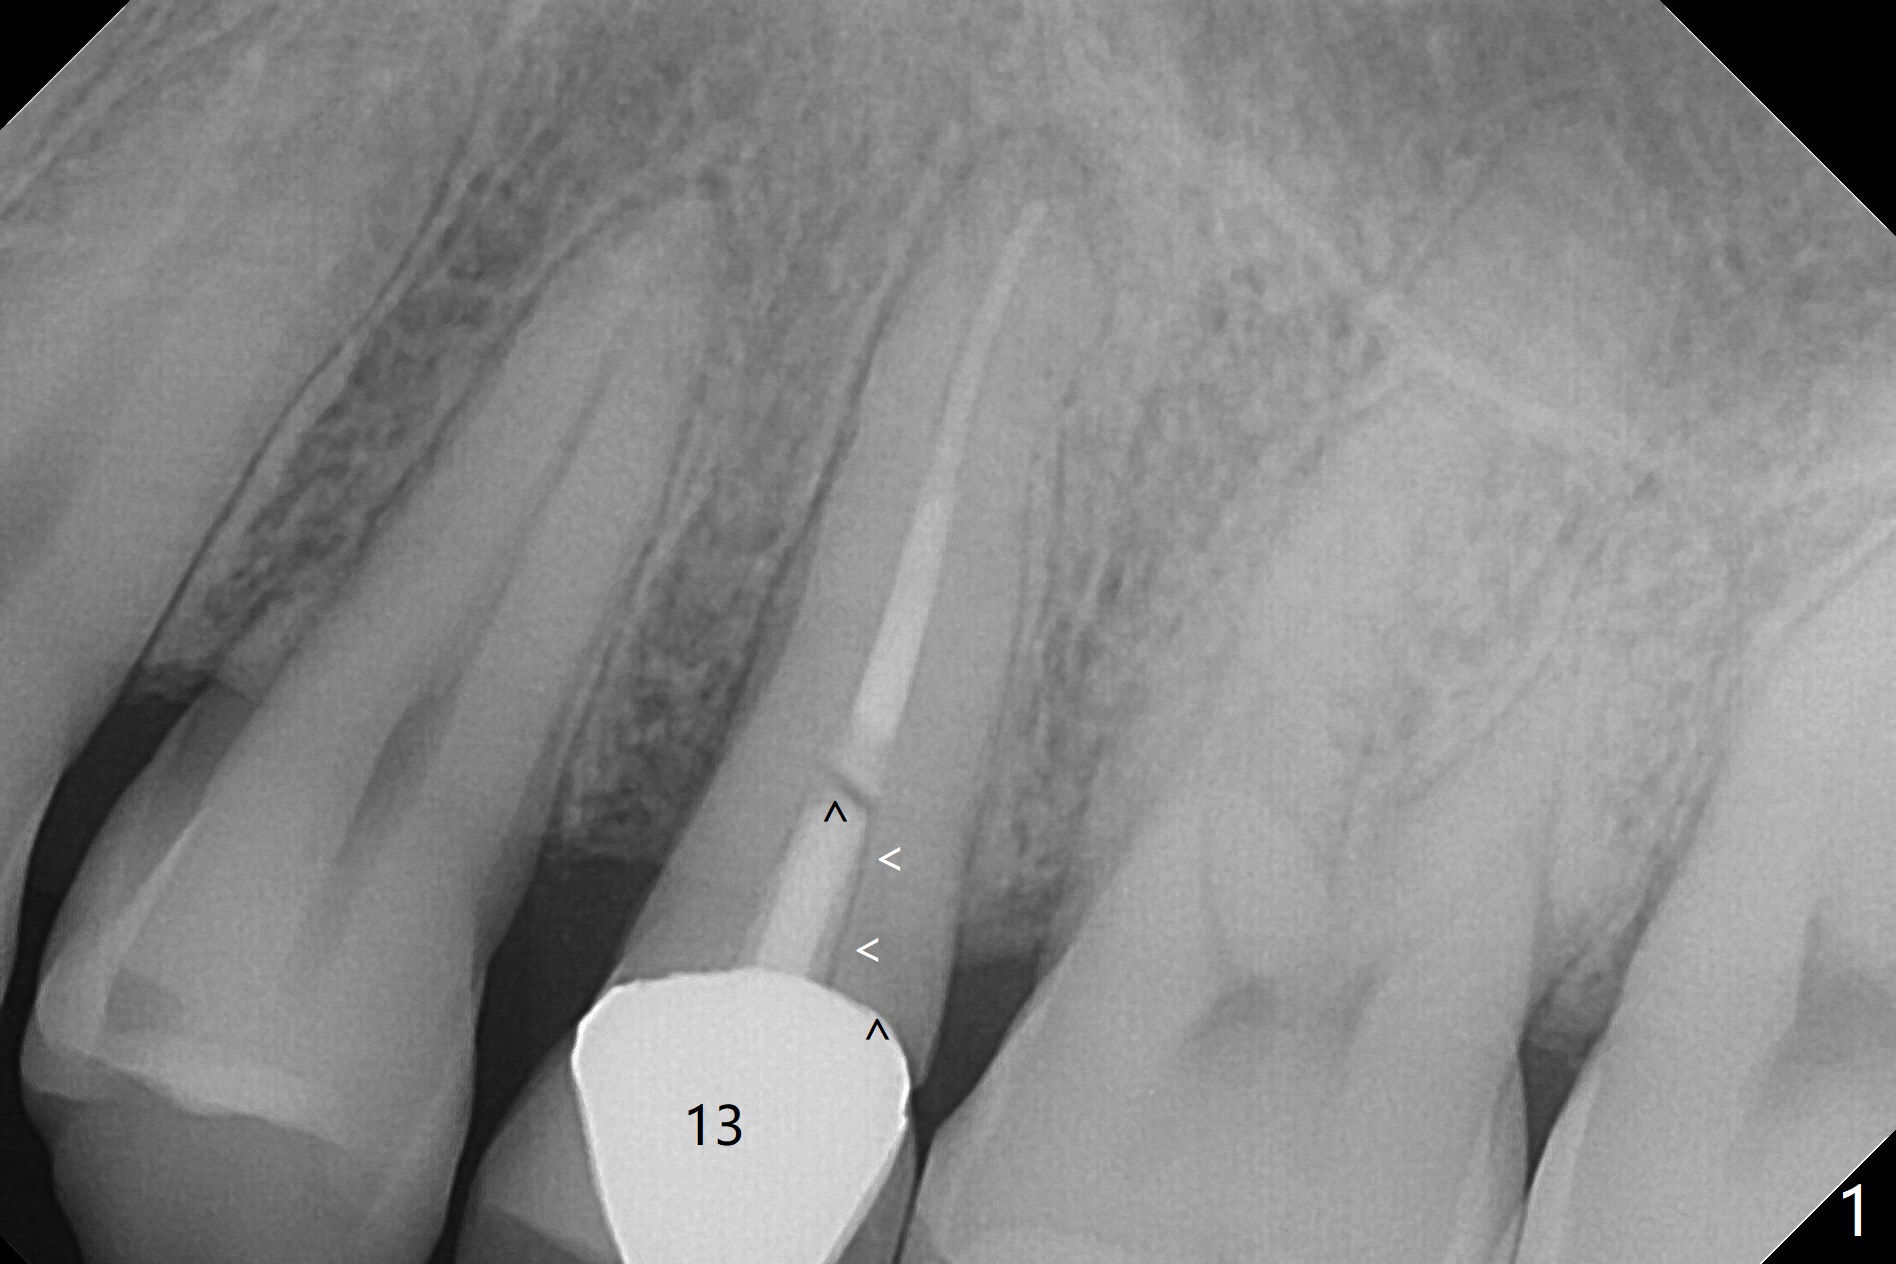

A 56-year-old man returns with chief complaint of a loose upper left tooth. Exam reveals fractured root (Fig.1 arrowheads). The apex is close to the sinus (Fig.2 (CT coronal section) S (B: buccal)). After extraction (Fig.3), start initial coronal osteotomy with a guide (Fig.4 red), ~ 1 mm from the sinus floor. Following sinus lift, PRF and bone graft (Fig.5 yellow circles), finish apical osteotomy and place a 4x15 mm implant (Fig.5,6). An angled abutment is expected (15 degree, Fig.5).